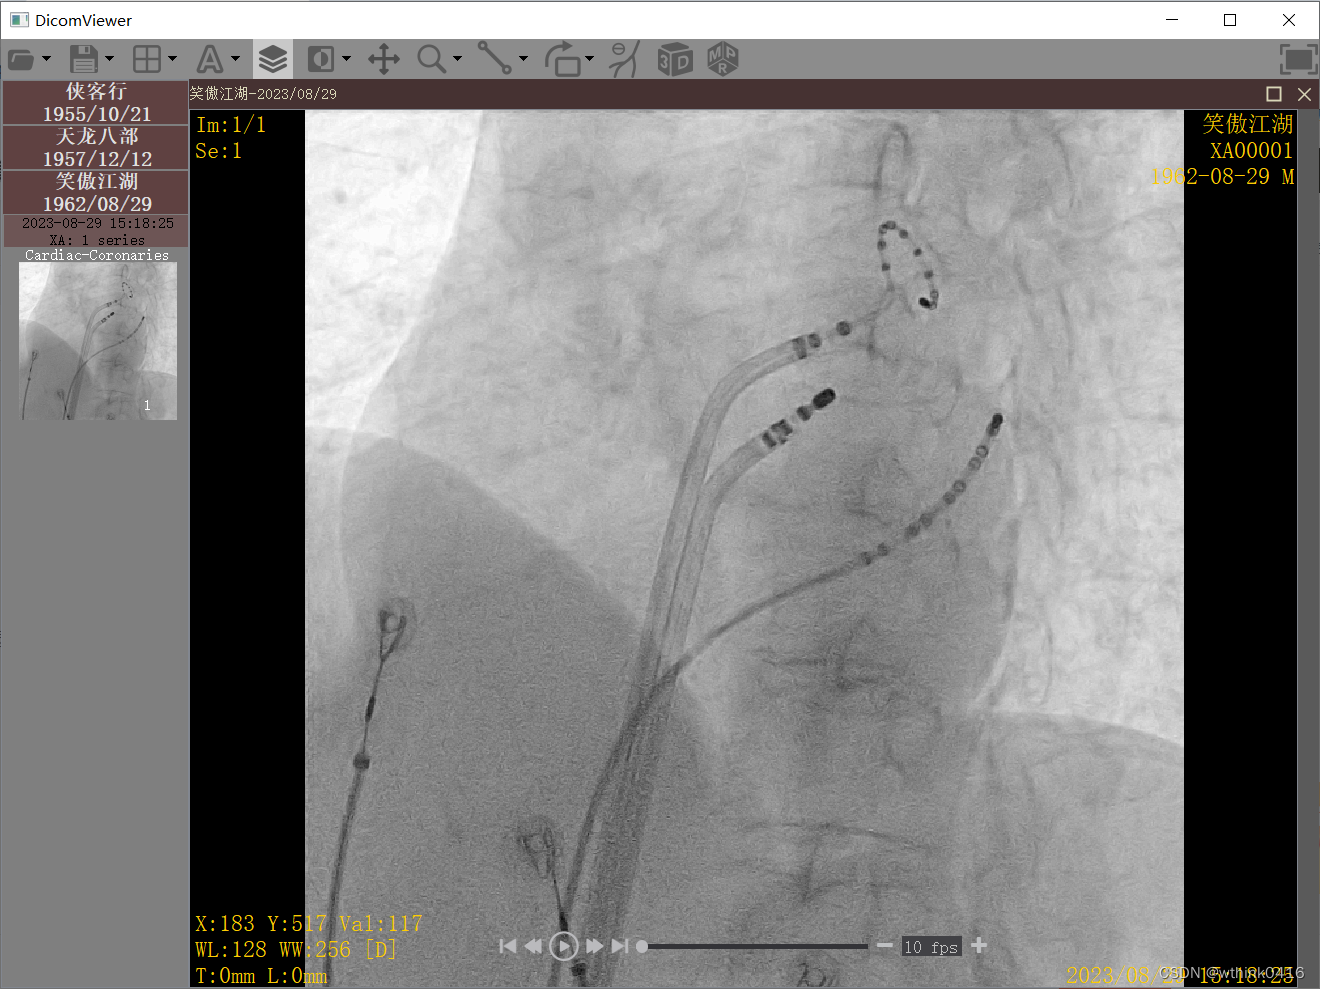

10、打开一幅DSA图像,支持播放、暂停、快进、快退、调整帧率等功能,同时可以手动拖拽播放进度条实现任意位置播放。